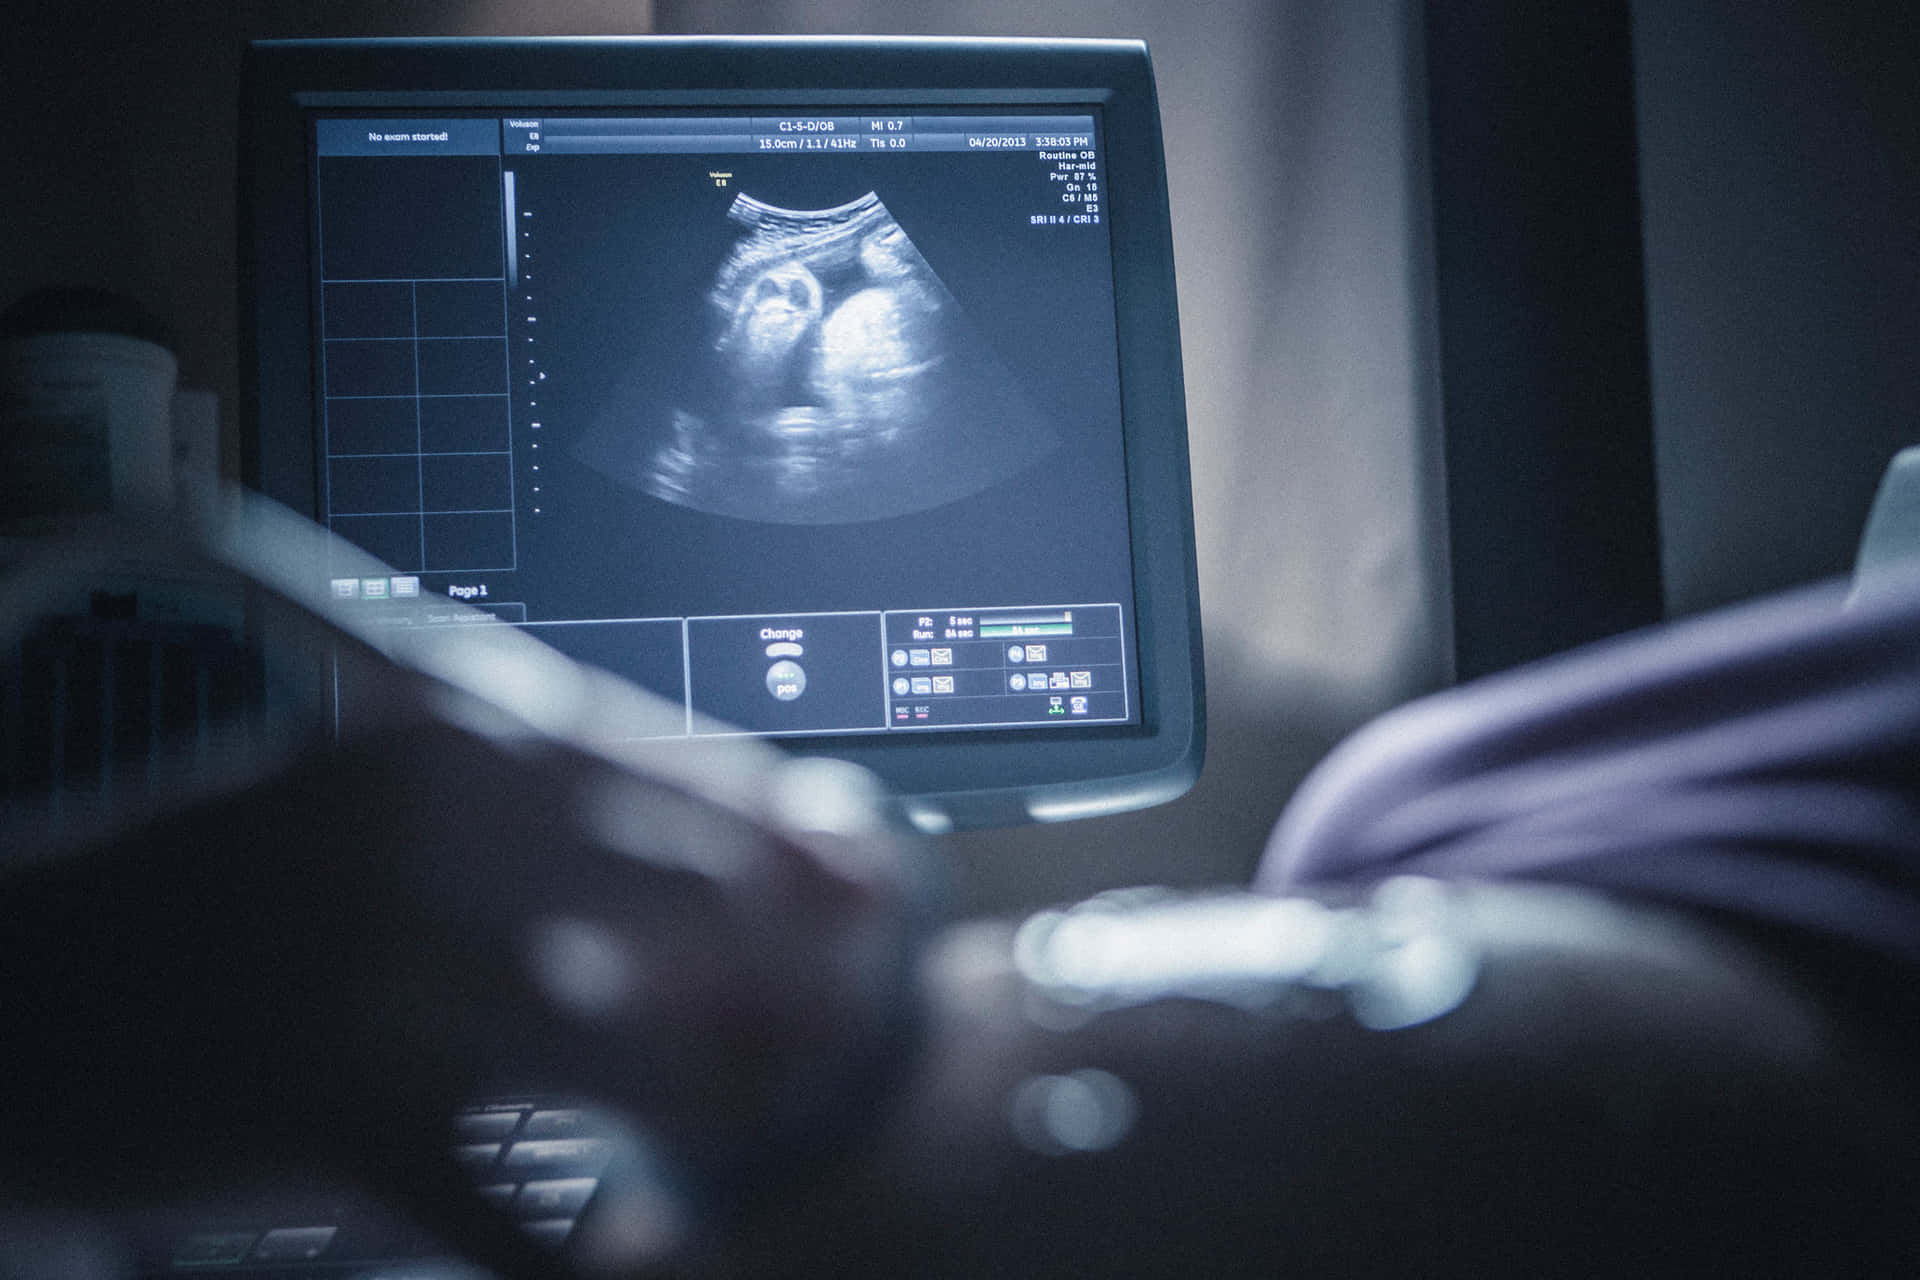

Ultrasound Department

At Lite Medical Diagnostics, we provide high-quality ultrasound diagnostic services using advanced technology and expert clinicians. Ultrasound is a non-invasive medical procedure that uses high-frequency sound waves to create detailed images of internal body structures. It’s a versatile and vital tool for diagnosing and monitoring a wide range of medical conditions.

• 1st Trimester Pregnancy Ultrasound

• Gynecological and Obstetrical Ultrasound (GYN/OBG)

• 3rd Trimester Pregnancy Ultrasound